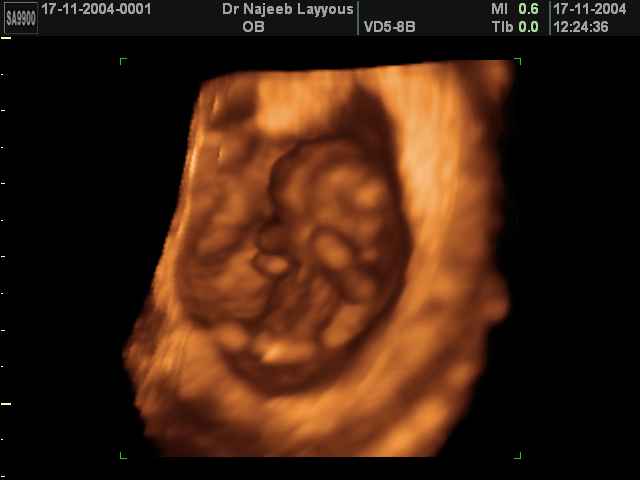

- First Trimester Ultrasound Photos

3D First Trimester Ultrasound Scan Photos ( Early Pregnancy Ultrasound Photos ) | Dr N Layyous